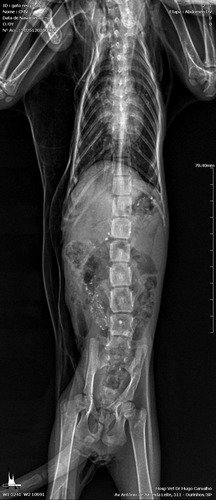

Deixo o raio x que foi feito hoje: